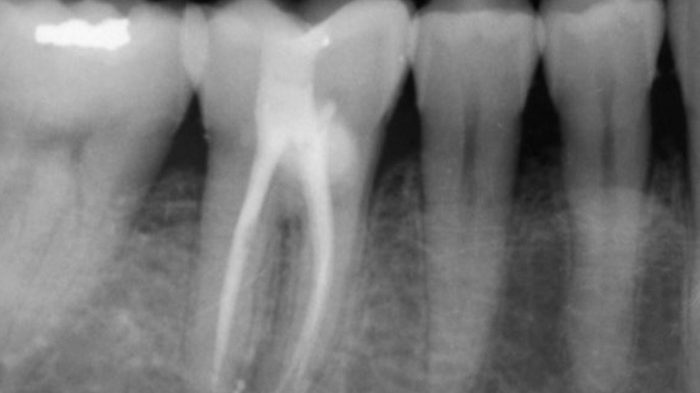

Necrosis pulpar en diente 45 con bifurcación en el tercio medio del conducto Caso clínico del doctor Francisco…